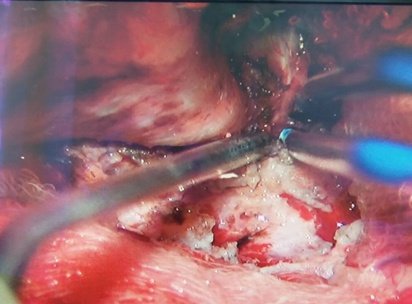

Пухлина видалена тотально (в товщі пухлини проходили передня та середня мозкові артерії, задня сполучна артерія та передня хоріїдальна артерія), також виконана декомпресія канала зорового нерва. Для адекватного доступу використовувався Neuro High Speed Drill краніотом з мікробороми.

При операції використовувся також єдиний в області кавітаційний ультразвуковий аспіратор, який дав можливість мінімізувати крововтрату та зберегти важливе васкулярне русло.